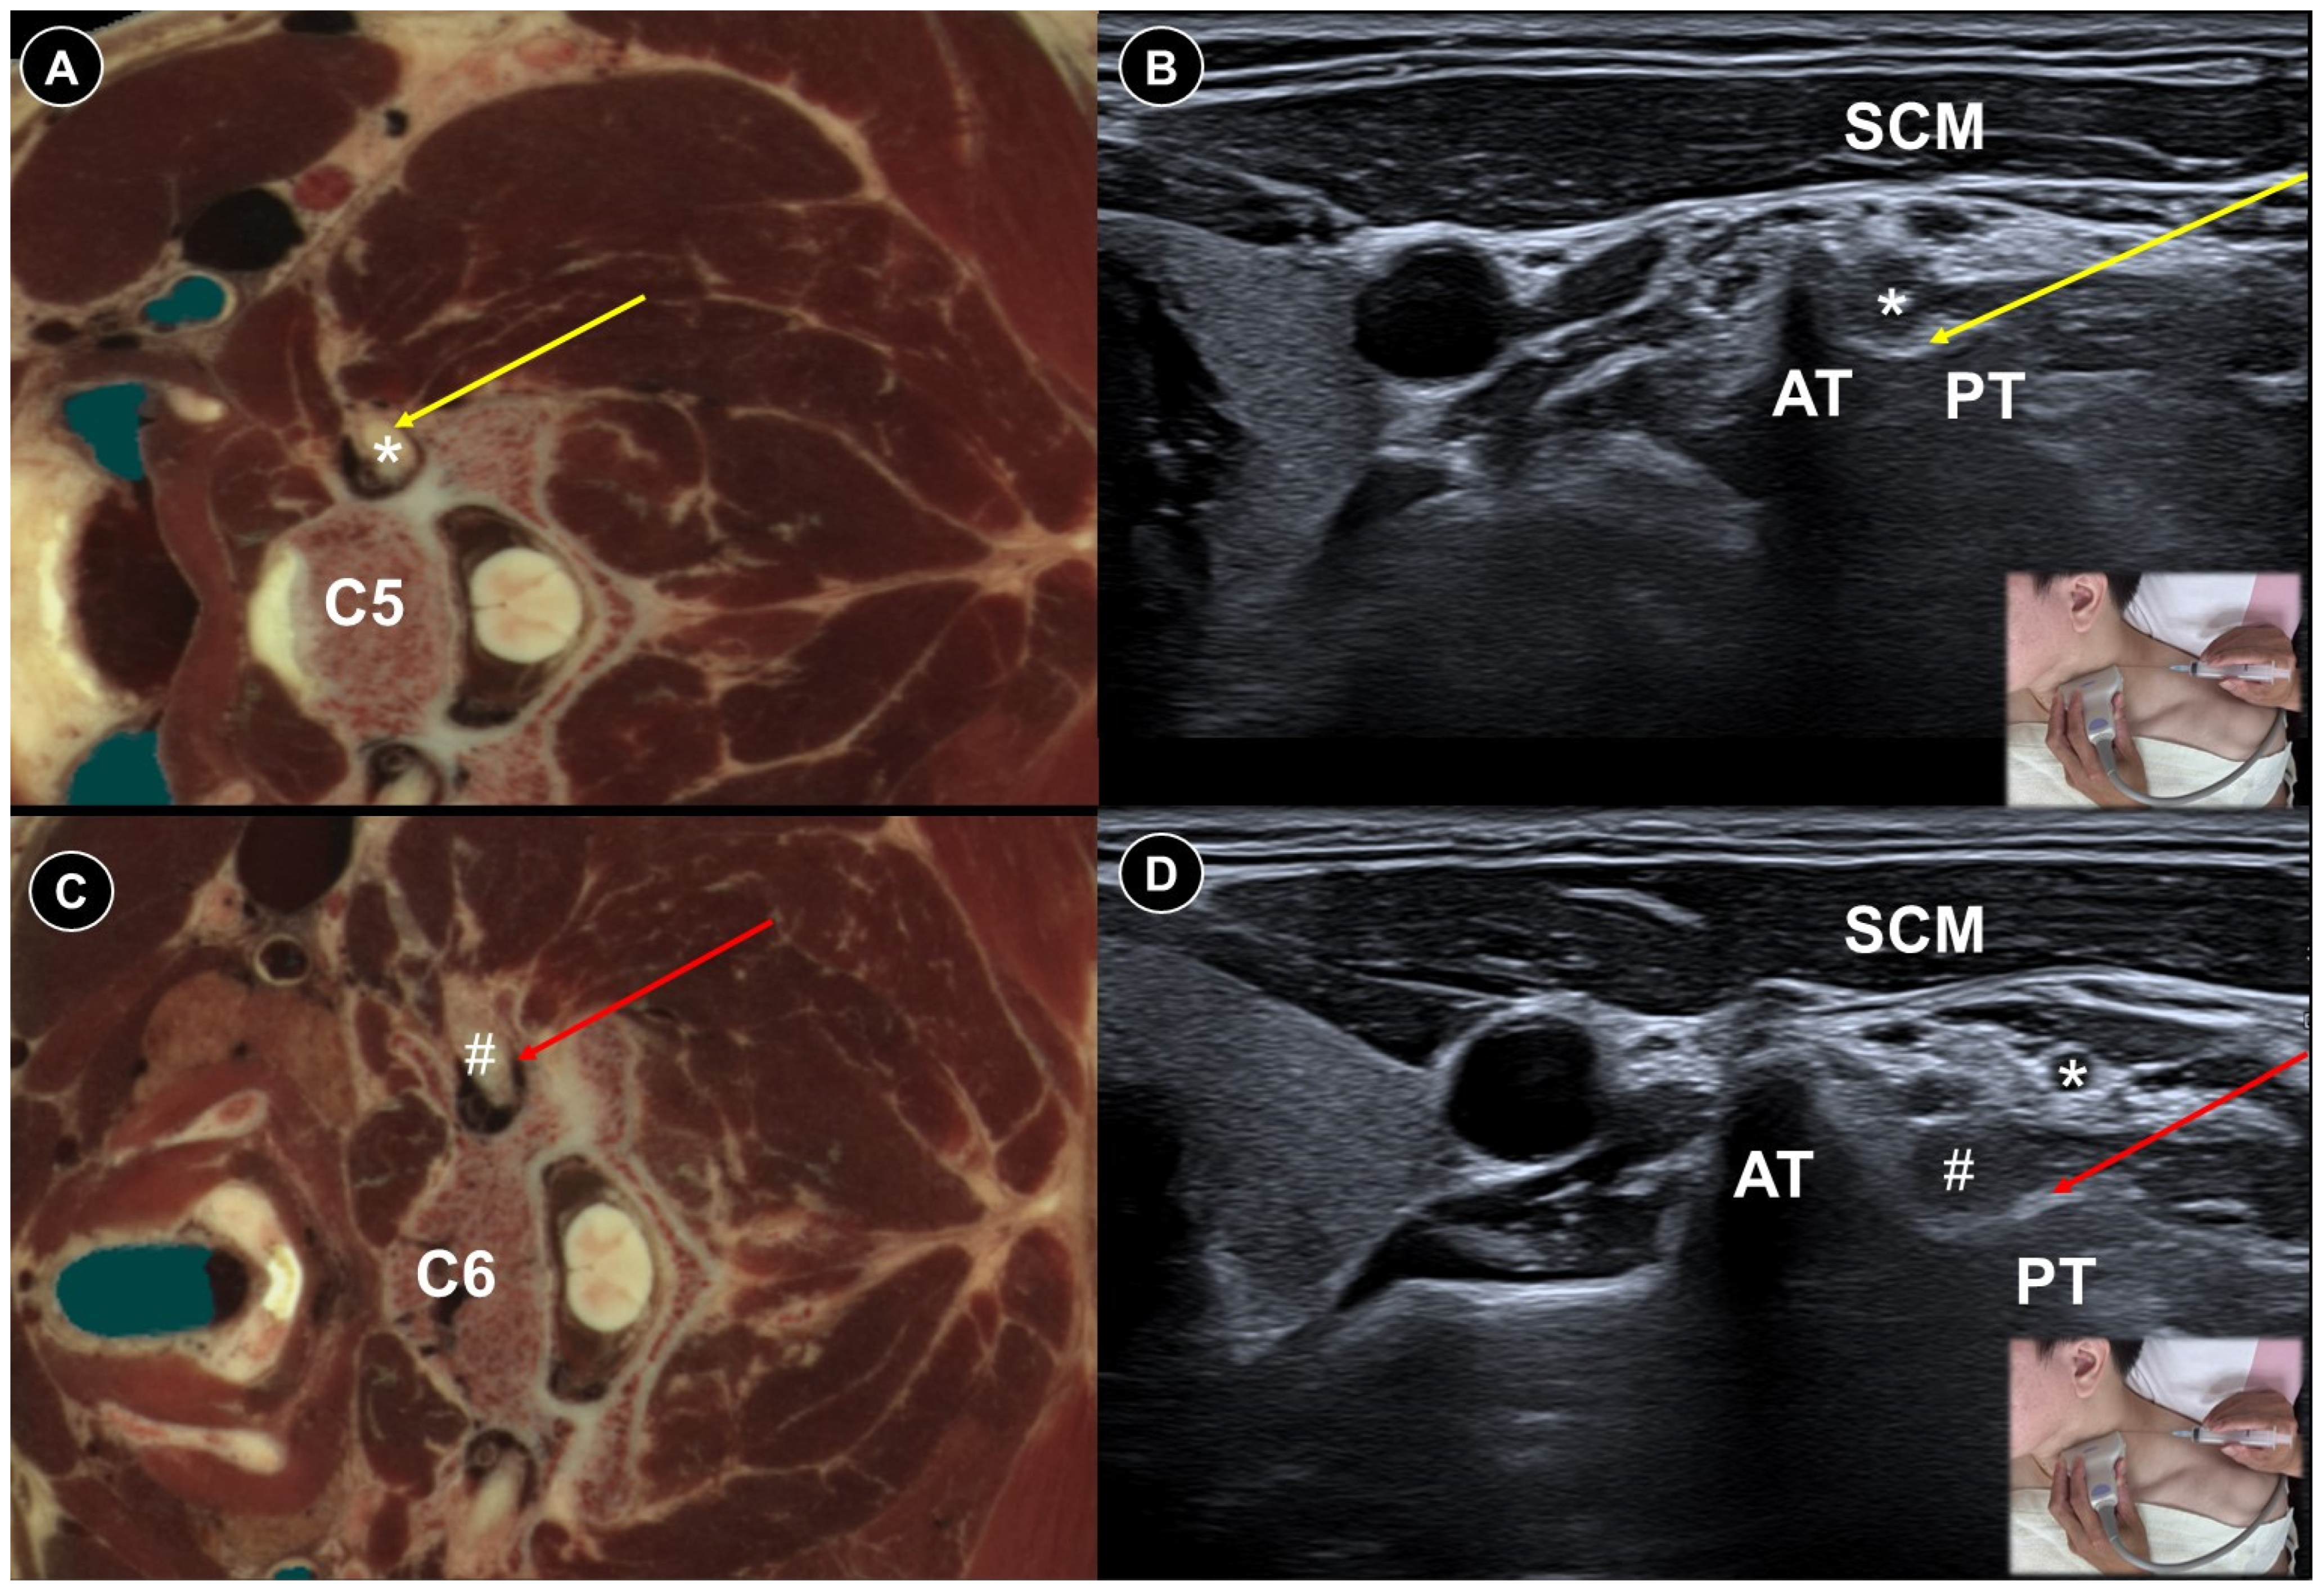

| Acute herpes pain | Burning, stabbing, or itching pain in the affected dermatomal distribution | Reactivation of VZV leading to viral nerve damage and inflammation | Cervical: supine, head turned to contralateral side Thoracic: prone | Cervical:

| Painful radiculopathy | Pain, numbness, clumsiness and even weakness in the distribution of the affected nerve root | Mechanical compression and inflammatory irritation of the nerve root, often due to disc herniation or spondylosis | Cervical: supine, head turned to contralateral side Lumbar: prone | Cervical: linear, in-plane

| Improvement of pain by ESI (meta-analysis), SNRB/caudal block (RCT) |